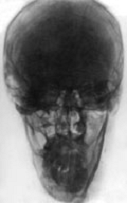

Вид спереди.

1-крыша (свод) черепа;

2-лобная кость;

3-лобная пазуха;

4-ячейки решетчатой кости;

5-костная перегородка полости носа;

6-передняя носовая ость;

7-межверхнечелюстной шов;

8-нижняя челюсть;

10-полость носа;

11-верхнечелюстная пазуха;

12-сосцевидный отросток;

13-глазница.